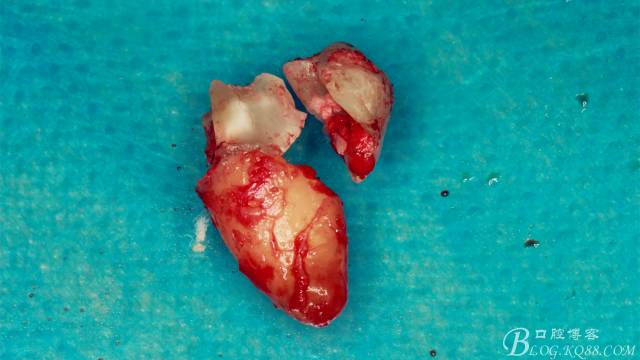

牙齒分為了三部分。